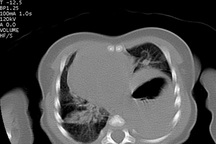

Tại đây, kết quả xét nghiệm, siêu âm ổ bụng và chụp X-quang của bé cho thấy hình ảnh dạ dày, quai ruột chiếm toàn bộ phổi trái, chèn ép đẩy lệch tim sang bên phải. Tình trạng này nếu không được mổ kịp thời để sắp xếp lại vị trí các tạng trong ổ bụng và lồng ngực, bé có thể tử vong bất kỳ lúc nào.

Sau khi hội chẩn kèm điều trị hồi sức tích cực, bệnh nhi được phẫu thuật nội soi cấp cứu. Quá trình phẫu thuật, ekip điều trị phát hiện toàn bộ ruột non, ruột già, lá lách thoát vị chui lên lồng ngực, nằm hoàn toàn trên khoang màng phổi. Trải qua hơn một giờ khẩn trương, các bác sĩ đã đưa các tạng thoát vị từ ngực về ổ bụng cho bé và khâu phục hồi cơ hoành khiếm khuyết.